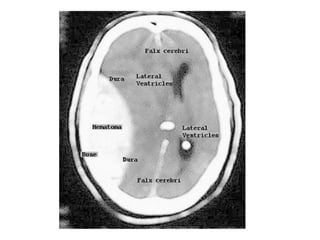

b) Radiological Findings :

*CT :

-Acute thrombus is hyperdense on precontrast CT

and expands the occluded sinus / vein (Dense

clot sign)

- Cord sign : is defined as a homogeneous ,

hyperattenuated appearance of thrombosed

venous sinuses , the hyperattenuated

appearance of the affected veins often being

named (the attenuated vein sign)

-Postcontrast :

1-Filling Defect : demonstration of contrast-filling defects

in the involved sinus or vein

2-Empty Delta sign :

*The sign consists of a triangular area of enhancement

with a relatively low-attenuating center which is the

thrombosed sinus

*In early thrombosis the empty delta sign may be absent

and you will have to rely on non-visualization of the

thrombosed vein on the CECT

*The sign may be absent after two months due to

recanalization within the thrombus

Direct visualization of a clot in the cerebral veins on a non enhanced

CT scan is known as the dense clot sign

Dense clot sign in a thrombosed cortical vein

CT without contrast : Cord Sign , in the SSS (dotted arrow)

and the RTS (arrows)

Attenuated vein sign in both ICVs (thin arrows), in the SS (crossed arrow)